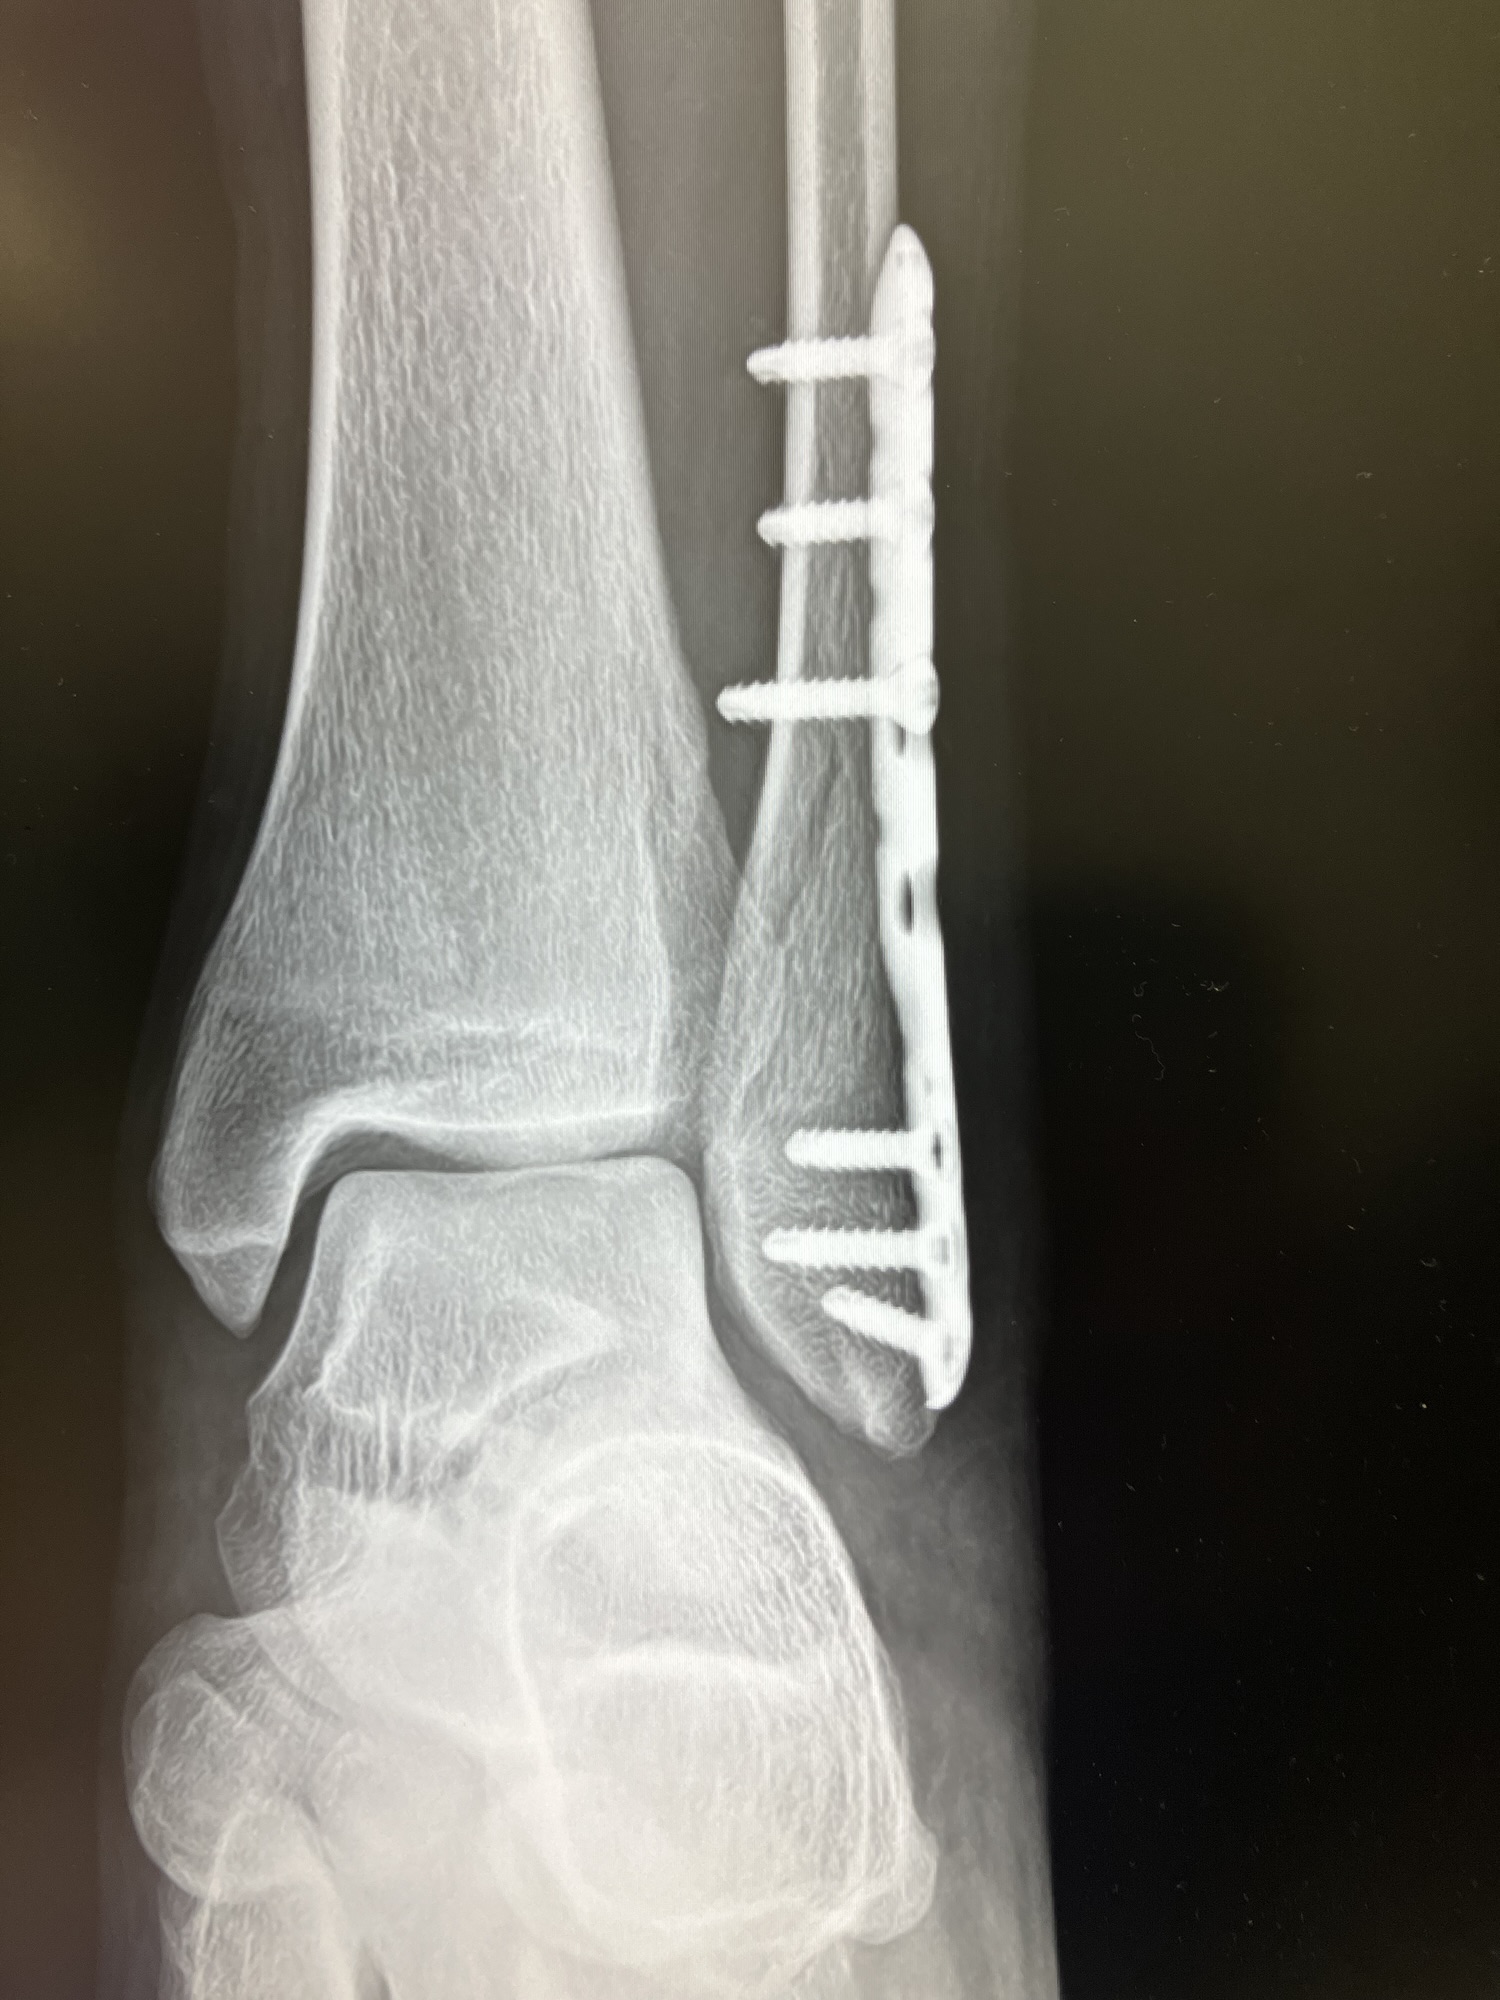

足を折ってから、松葉杖で生活しています。